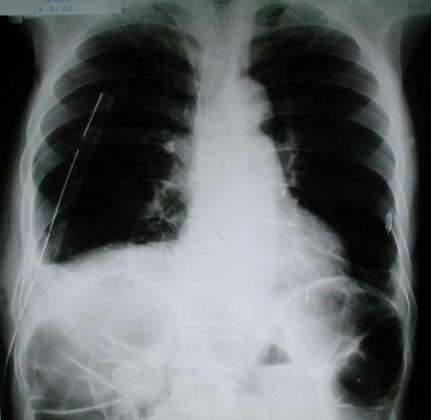

Radiología Pos operatoria

• La radiografía de control pos operatoria inmediato (12 horas), demuestra un diafragma derecho conformado, altura adecuada en relación al diafragma izquierdo, pulmón derecho expandido, escaso líquido pleural residual, asas intestinales distendida por contenido aereo, aguja de cateter venoso subclavio.